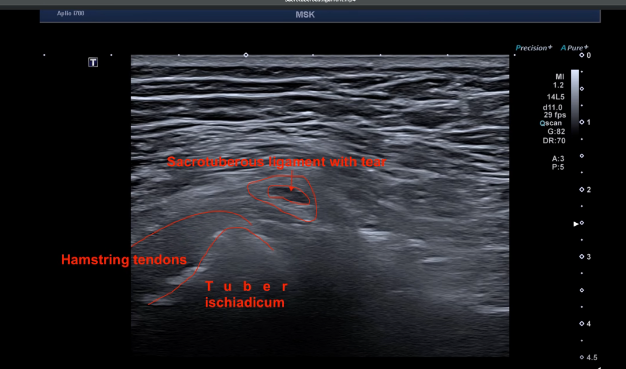

【超声诊断与治疗】 为进一步明确痛点,对患者进行了肌骨超声(MSK Ultrasound)探查(见附带超声动态视频)。 超声发现: 在患者主诉的最高痛点处,清晰显示骶结节韧带(Sacrotuberous Ligament)撕裂。 治疗方案: 针对骶结节韧带行增生疗法(Prolotherapy) + 针对股后皮神经行水分离术(Hydrodissection)。 治疗结果: 术后患者疼痛即刻获得完全缓解。

- 易漏诊的痛点: 骶结节韧带是臀部疼痛中极易被忽视的来源。当常规 MRI 发现的病灶(如腘绳肌损伤)无法完全解释患者的体征时,需结合高频超声进行痛点精准探查。